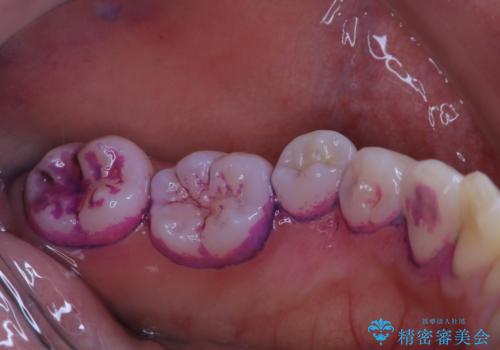

染め出しを行い、どこに歯ブラシが当たっていないか確認し、ブラッシングの改善ができるように指導も行いました。

染め出しをしてみると、べったりとプラークが付着していることがわかります。プラークが長い間付着したままだと、歯石となり歯ブラシだけでは取り除くことのできない状態になります。

また、PMTCでは専門的な機械や材料を使用して汚れを除去していくため、虫歯や歯周病・口臭予防にもなり、定期的に行うことで、お口の健康維持につながります。